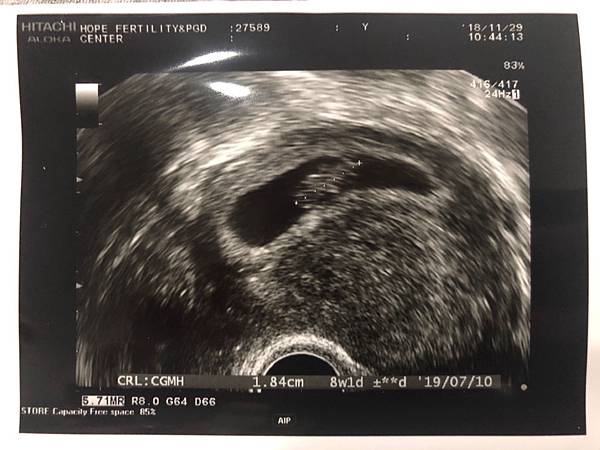

———— 11/29 8W2D ————

這2次回診,R都比我還要期待,今天在超音波下,看到快速跳動的心跳,頭、手和身體也都變清楚了,還可以看到這麼渺小的身軀在舞動著,感覺好神奇。R一直微笑,感覺到他很滿足很快樂。還有好消息就是沒有看到出血了,但12週前都還是屬於不穩定期,還是需要盡量休閒,動作不要太大。